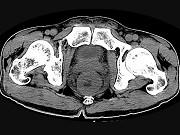

问题 男,56岁,排便形状改变,便不尽感,CT检查如图所示,下列说法正确的是()

选项 A.肠壁上有蒂状新生物 B.其表面光滑,边界清楚 C.肠腔未见狭窄 D.此为直肠息肉 E.此为直肠癌

答案 E